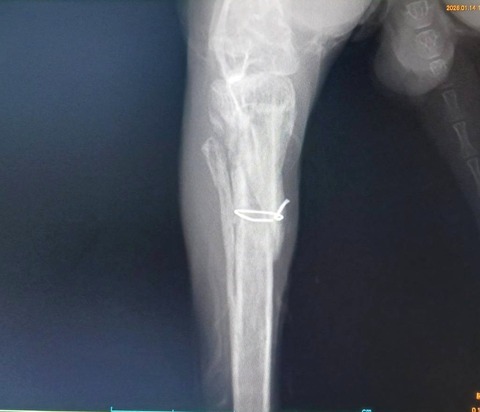

2025年11月に右後ろ脚を骨折し、11/14にピンニング手術を受け、現在も経過観察中です。

1/10 経過の診察を受けました。

足の曲げ伸ばしや太ももの筋肉の状態は良好で、まだ力は弱いものの、自分の足で押し返そうとする反応が見られました。

レントゲンでは骨の形成は概ね順調でしたが、固定していたピンのうち1本が抜けてきていることが確認されました。

このため、早めにピンを抜去する方針となりました。

1/14 ピン抜去手術

予定通り2本のピンを抜去し、手術は大きな問題なく終了しました。

足の可動は保たれているものの、レントゲン上では膝の骨がやや前方に出ており、過去に靭帯を損傷していた可能性があるとの説明を受けました。

将来的に関節への負担が出る可能性はありますが、現時点では慎重に経過を見ていくことになりました。

術後は運動量を制限し、内服薬を使用しながら回復を待ちます。